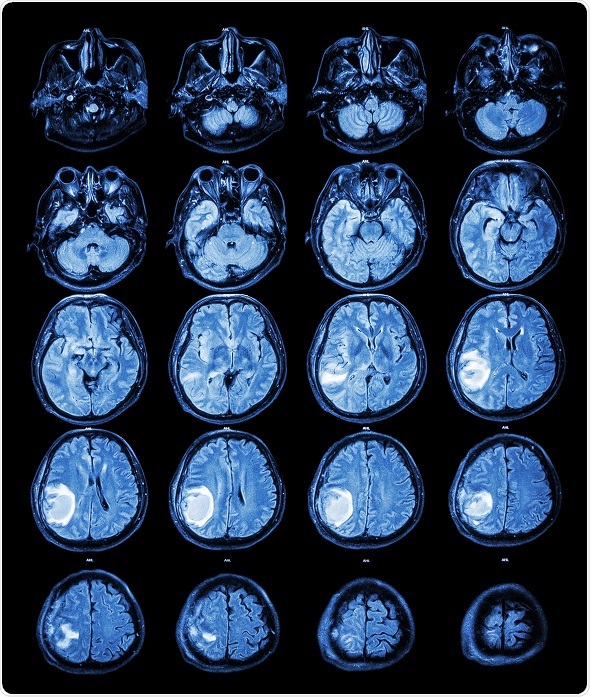

Image

MRI: Brain tumour at right parietal lobe.

Although the need for full tumor resection is an unmet need in various cancer types, it is particularly urgent in the field of brain cancer. Suboptimal results are often seen in patients who undergo brain surgery for high-grade tumors, with tumor recurrence often occurring close to the resection cavity. Furthermore, the removal of healthy brain tissue can have extremely detrimental consequences for these patients.